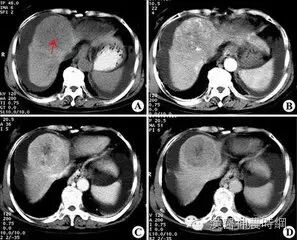

2.计算机X线体层扫描(CT)  CT是一种安全、无创伤、高分辨力的检查方法。对肝癌的定位诊断很有价值。CT能显示肿瘤的大小、位置、数目及与周围脏器和大血管的关系,可检出1cm左右的早期肝癌。并有助于了解是否伴发肝外转移,如肝门淋巴结,胰头后淋巴结等。结合增强扫描可以判断病变的性质,对肝癌与肝血管瘤的鉴别有较大的价值。平扫下肝癌多为低密度占位,边缘清晰或模糊,部分有包膜的肝癌可显示晕圈征。较大的肝癌可见更低密度的坏死区,少数肝癌可见钙化。增强扫描有滴注法、大剂量推注、推注加动态扫描等。

肝癌在动脉期尤以注药20s内强化最为明显,癌灶密度高于周围肝组织。30~40s后造影剂进入细胞间隙转入实质期,病灶又恢复为低密度,显示更为清晰。近将肝动脉造影与CT检查相结合,开展CT动脉造影(CTA)和CT动脉门脉造影(CTAP),对提高小肝癌的检出率有一定价值。也有人在CT检查前一周经肝动脉插管注入碘化油(lipiodo1),再做CT扫描,这种lipiodol-CT可检出0.5cm的小肝癌。对于<1cm的肝癌,Uchida报告US、CT、肝动脉造影和几种CT检查的分辨力为:US 63%、普通CT 12%、滴注法增强扫描65%、CTA 71%、CTAP 80%、lipiodol-CT 89%。